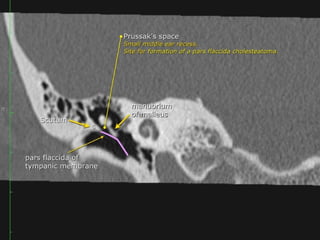

-Prussak space (superior recess), this space is marginated by the pars

flaccida and scutum laterally, the lateral malleal ligament superiorly,

and the neck of the malleus medially

The tympanic cavity

 Medial wall

contains the oval and round window and the prominence of the

tympanic segment of the facial nerve.

 Lateral wall

is mainly formed by the tympanic membrane. The scutum is the bony

prominence at the upper part or pars flaccidum of the tympanic

membrane.

Tympanic membrane

 The tympanic membrane or eardrum is a cone-shaped membrane

that separates the external ear from the middle ear.

 The pars flaccida is the upper fragile part that is associated with

eustachian tube dysfunction and cholesteatoma.

 The pars tensa is larger and more rubust and associated with

perforations.

The handle or manubrium of the malleus is connected to the central

part of the tympanic membrane, which is called the umbo.

Acquired Cholesteatoma :

39 year old F with left conductive hearing loss.

Click to Return to Algorithm

A: CT Rt axial

B: CT Rt cor

C: CT Lft axial

D: CT Lft cor

Normal

Scutum

Soft tissue density within the

middle ear cavity. It

obliterates Prussak’s space

and erodes the scutum and

ossicles.

Clear

Middle

ear

cavity